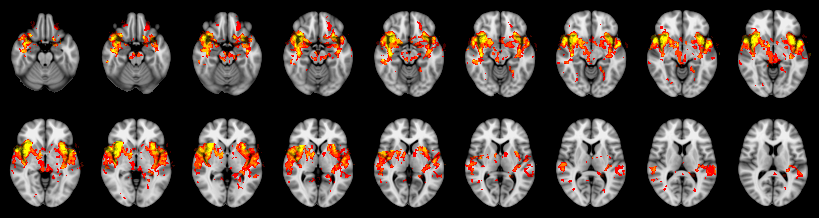

Pain study, TFCE, Uncorrected

Combined

Stouffer: